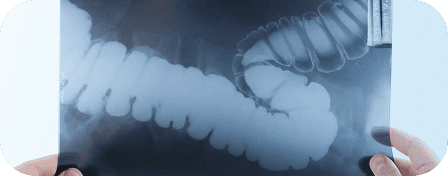

Mucha gente desconoce el poder que tienen nuestros riñones en el envejecimiento. Y cuando hablo de gente me refiero a la sociedad en general, pero también a los propios sanitarios; e incluso a los nefrólogos. En los riñones se encuentra la proteína klotho, un elemento clave en la longevidad que fue descubierta en 1997, hace apenas 30 años, por el científico Makoto Kuro-o.

A través de diversos experimentos en ratones, entendió que cuando suprimía la función de la proteína klotho, se inducía en estos animales un envejecimiento precoz. Concretamente, sus vasos sanguíneos, su piel, su cerebro o su riñón condicionaban que los ratones fallecieran

cuando eran adolescentes; un caso similar al de Benjamin Button, pero al revés.

La función de klotho en el riñón es eliminar el exceso de fósforo que se genera, principalmente en la dieta. Cuando realizamos ingestas elevadas de fósforo, este alcanza el riñón que tiene capacidad para excretar este elemento por orina y así evitar que se acumule en la sangre. Sin embargo, esta función es finita y cuando exigimos a nuestros riñones que eliminen mucho fósforo, klotho disminuye, con lo que ello conlleva en términos de supervivencia. Pero ¿qué alimentos son los ricos en fósforo? La respuesta es sencilla y directa: los ultraprocesados. El fósforo es un aditivo habitual en este tipo de alimentos procesados industrialmente y es muy frecuente encontrarlos en las etiquetas escondidos tras siglas como: